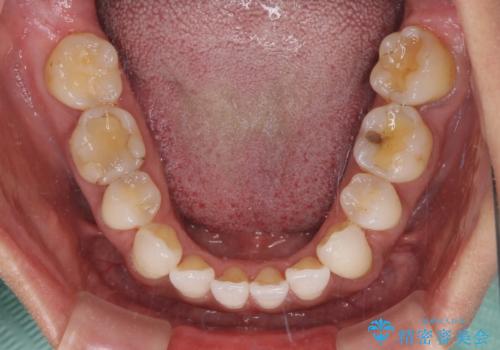

- 下顎前歯を中心に、以前行った矯正治療の後戻りが気になるとのことで来院された患者様です。

後戻りは軽度であったため、インビザライン・ライトにて治療を行うこととしました。